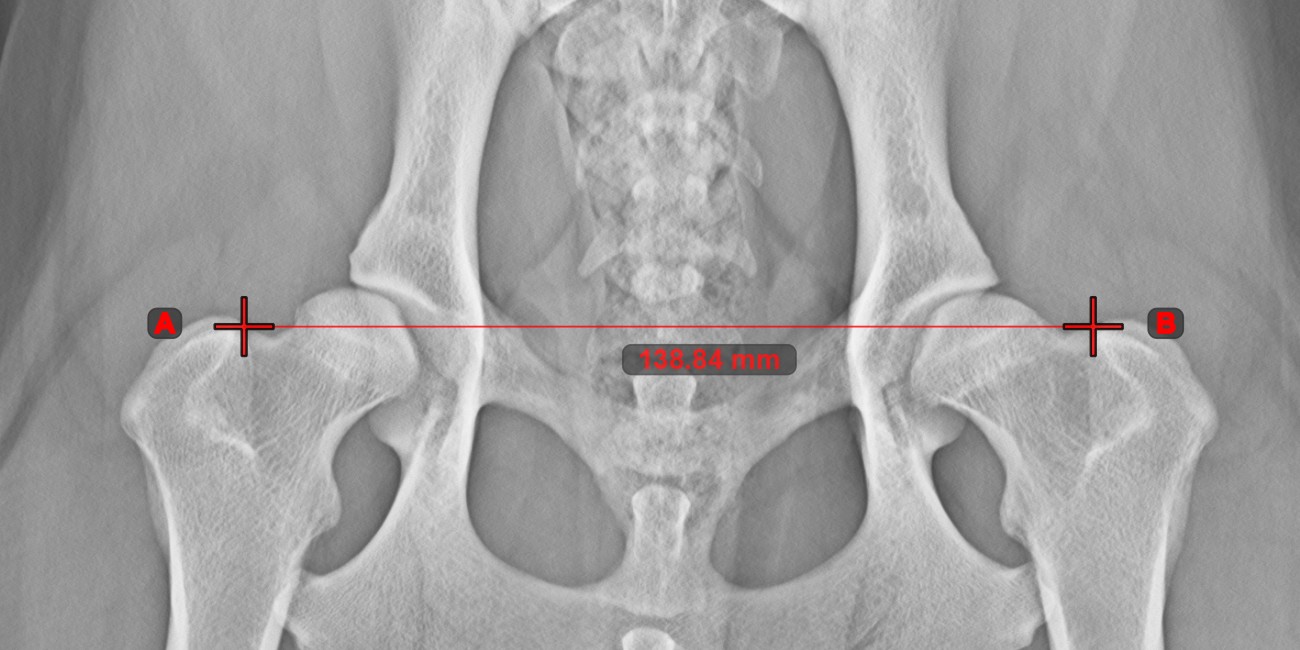

Linienmessung¶

Erstellen Sie eine Linienmessung, um den Abstand zwischen zwei Punkten mit hoher Genauigkeit zu berechnen.

Wählen Sie das Werkzeug Linienmessung aus und weisen Sie es einer der verfügbaren Maustasten zu. Setzen Sie die Start- und Endpunkte in der Szene oder wählen Sie sie aus bereits vorhandenen Punkten im Bild aus. Der Abstand zwischen den beiden Punkten wird automatisch anhand der Standardkalibrierdaten oder der durch die Längenkalibrierung-Messung neu kalibrierten Daten berechnet.

Ändern Sie den Start- und Endpunkt mit dem Werkzeug Objekt auswählen/verschieben. Der Abstand zwischen den beiden Punkten wird automatisch neu berechnet.